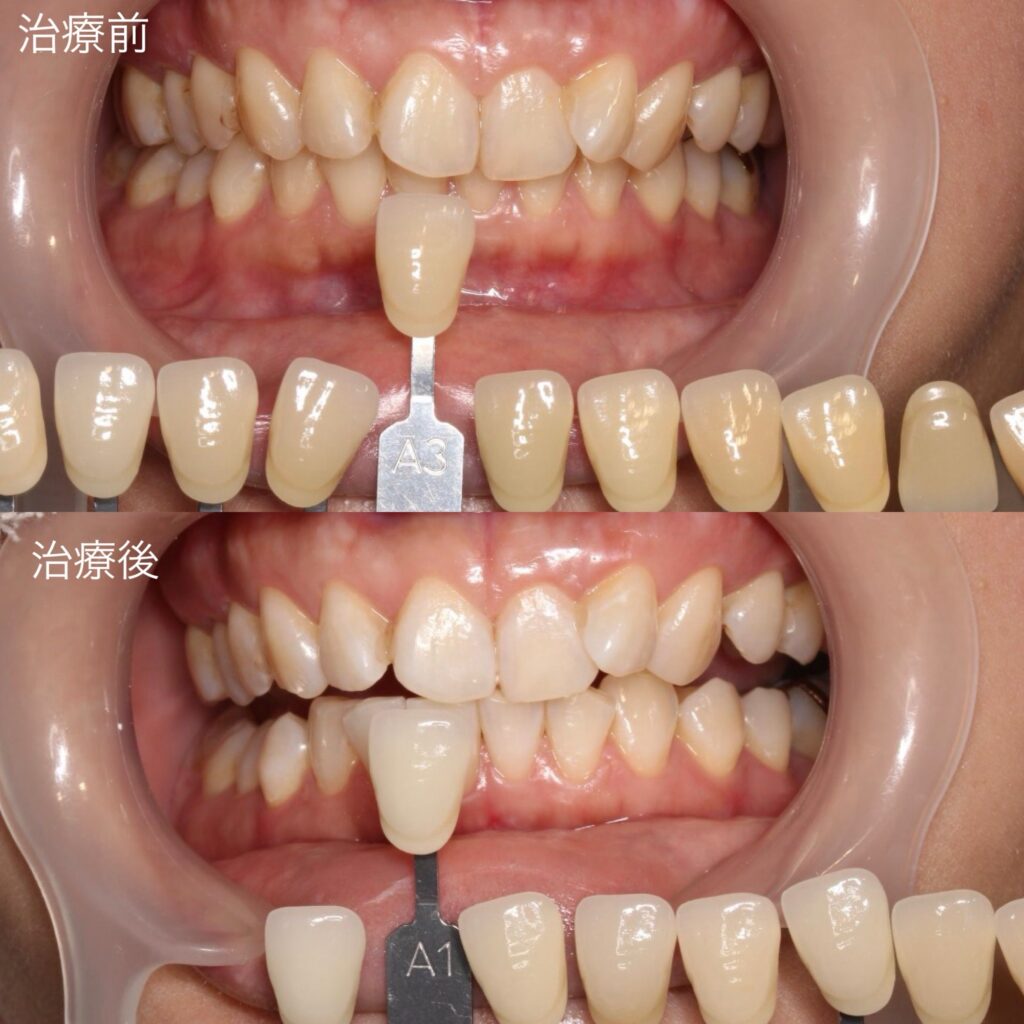

③ ホワイトニング

全体の歯を明るくするために、オフィスホワイトニングを行いました。神経のない左上の前歯は、ウォーキングブリーチを兼ねた特殊な方法で行いました。

初雁歯科クリニックでは、日本審美学会認定ホワイトニングコーディネーターの歯科衛生士が担当します。

全体のトーンが上がることで、「1本だけ浮く」印象を軽減できます。

④ 色調の変化

施術前:A3

施術後:A1

まで明るくなりました。

⑤ コンポジットレジン修復で仕上げ

神経のない歯は、ホワイトニングだけでは完全に周囲と同じ色にならないため、コンポジットレジン(白い詰め物)で色を調整し、自然になじませました。